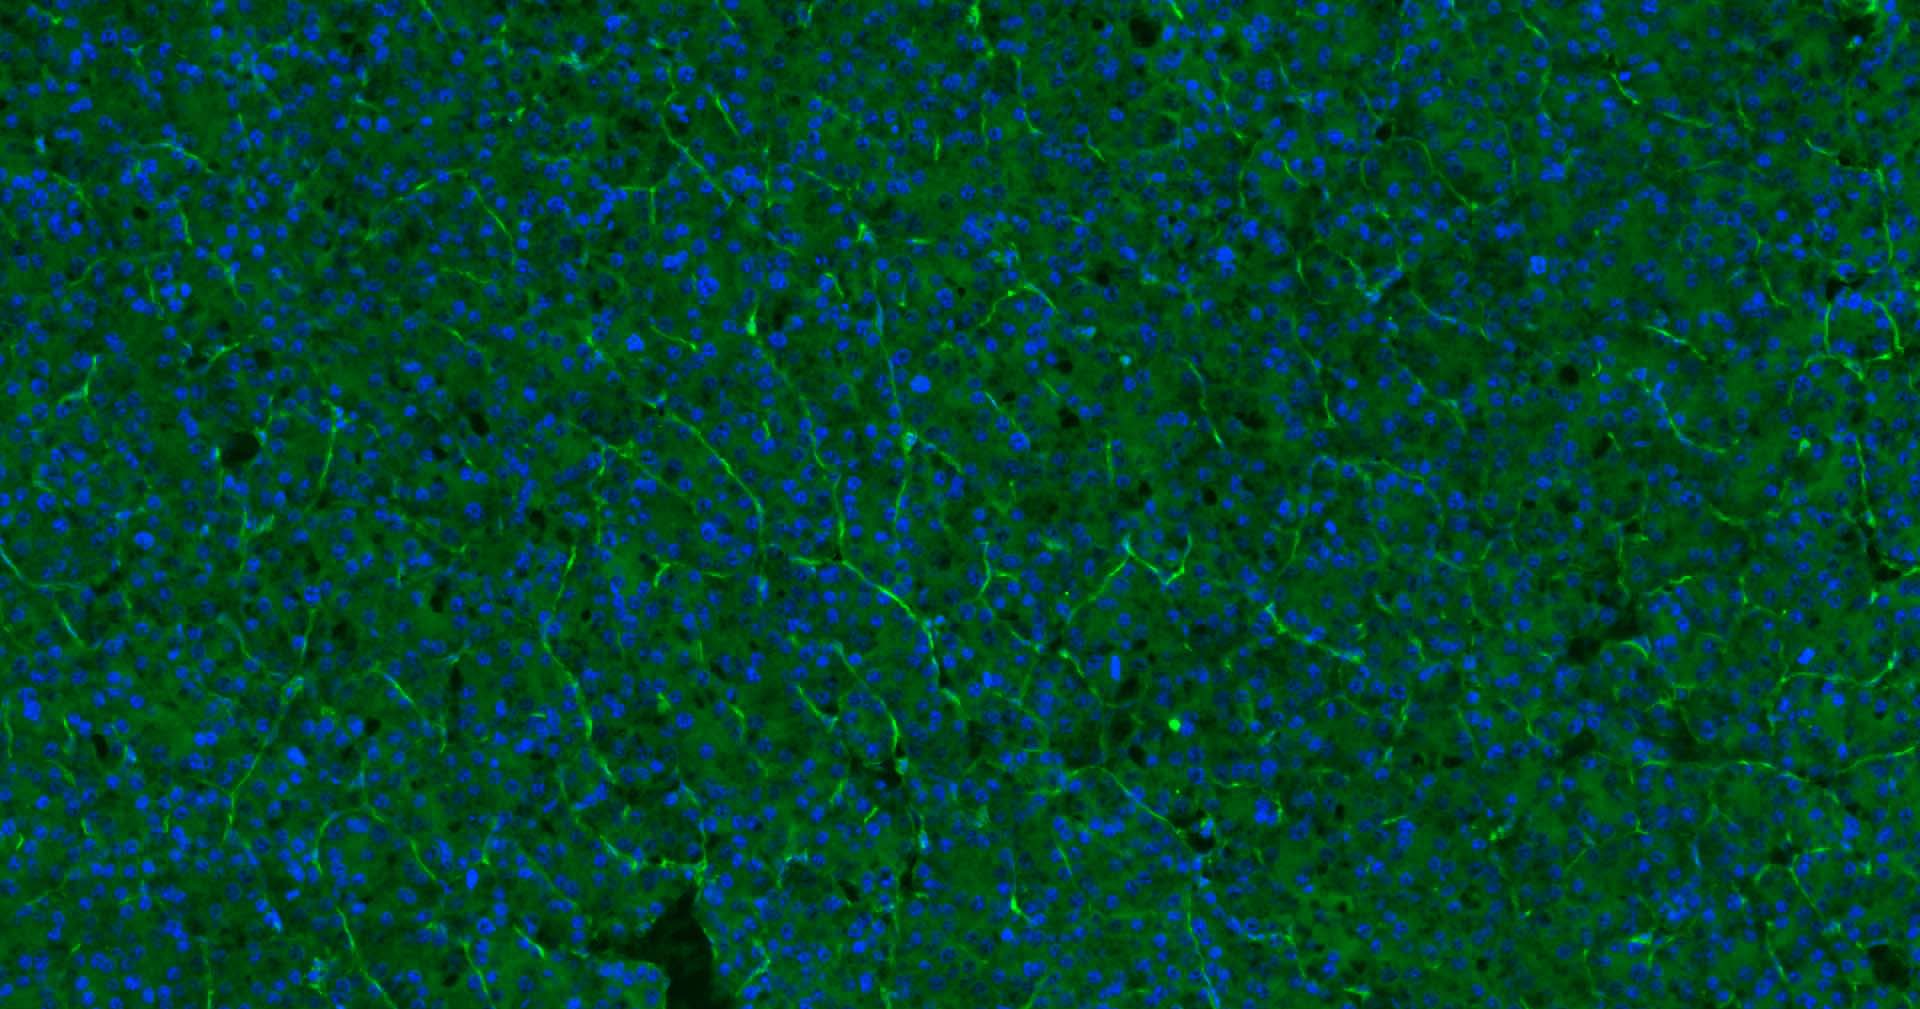

Paraformaldehyde-fixed, paraffin embedded Human Liver; Antigen retrieval by boiling in sodium citrate buffer (pH6.0) for 15 min; Antibody incubation with CD31 Monoclonal Antibody, Unconjugated (bsm-10825M) at 1:200 overnight at 4°C. Followed by conjugated Goat Anti-Rabbit IgG antibody (green, bs-0296G-BF488), DAPI (blue, C02-04002) was used to stain the cell nuclei.